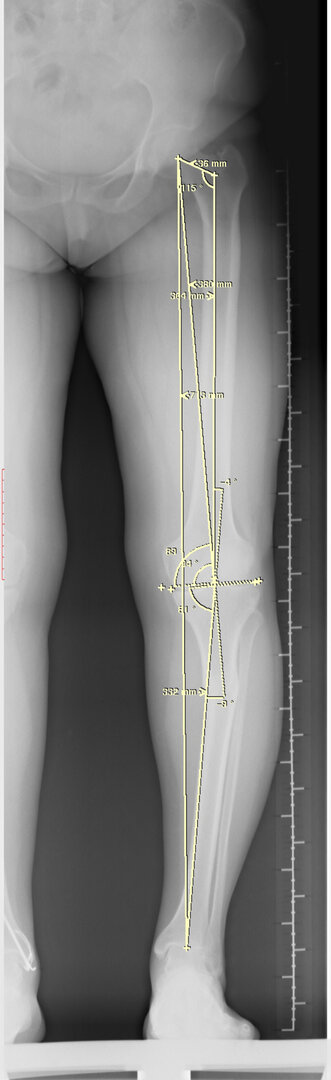

Normal bir kişide diz eklemi hafif içe doğru eğimlidir. Bunu genu varus olarak adlandırmaktayız. Bazen bu varus açısı fazla olduğu zaman diz ekleminin iç tarafına anormal yük binerek erken dönemde kireçlenme ortaya çıkmaktadır. Özellikle genç hastalarda bu durumun düzeltilmesi gereklidir. Aksi takdirde daha erken dönemde diz ekleminde problemler yaşamaya başlarlar.

Bu ameliyat öncesi bir deformite analizi yapılıp hangi kemikte, normalden ne kadar sapma olduğu tespit edilir. Daha sonra bu kemiğe yine ostetomi yapılarak bu anormal sapma düzeltilir.  Bu düzeltme plak-vida veya intramedüller çivi ile akut olarak düzeltilebileceği gibi bilgisayar destekli sirküler eksternal fiksatör ile tedrici olarak ta yapılabilir. Hangi yöntemin hangi hasta için uygun olacağına hasta özelinde karar veriyoruz, ne tür cerrahi tedavi olması gerektiğini danışabilirsiniz.